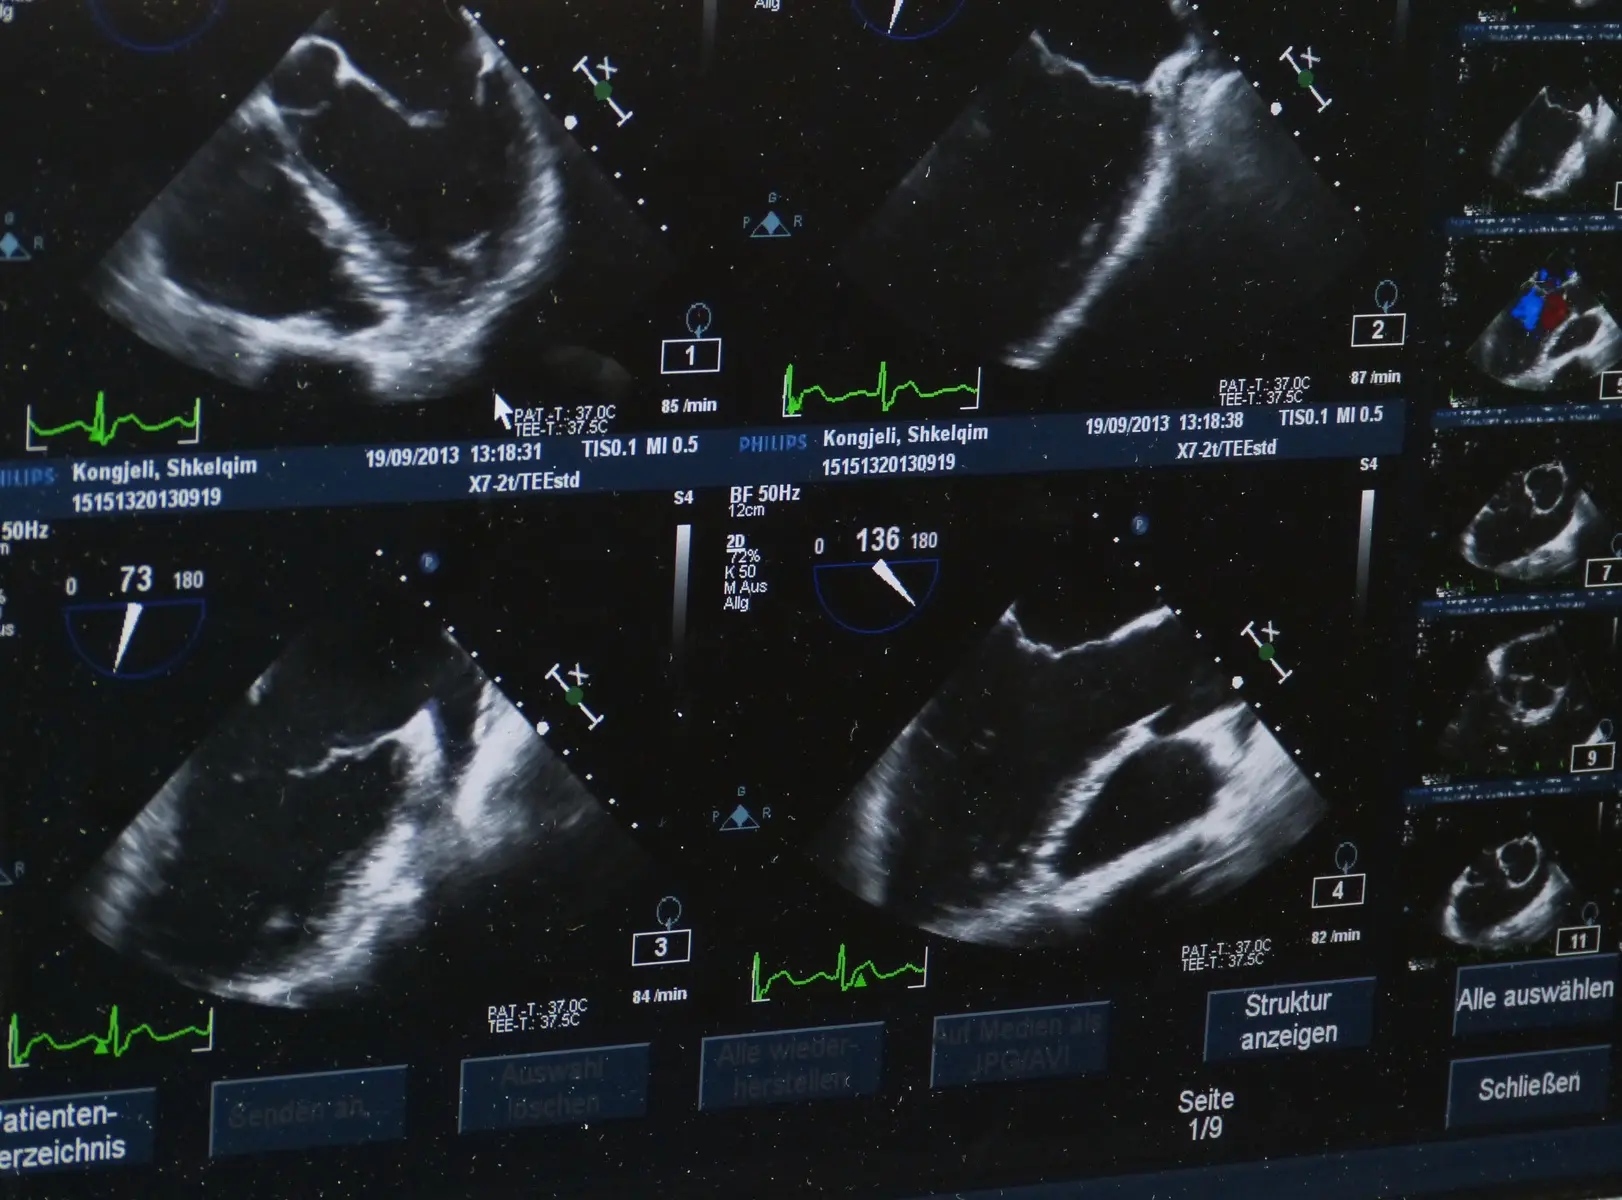

One of the key benefits of USG is its versatility. It is widely used across various medical disciplines, including obstetrics, cardiology, urology, and emergency medicine. In obstetrics, for example, USG plays a critical role in monitoring the development of the fetus, assessing the health of the placenta, and diagnosing potential complications early on. Cardiologists rely on echocardiography, a type of ultrasound, to evaluate heart function, detect abnormalities in heart valves, and diagnose conditions such as heart failure or congenital heart disease.

Moreover, USG’s real-time imaging capability allows for dynamic assessments. For instance, in emergency settings, point-of-care ultrasound (POCUS) can be used to quickly assess trauma patients, guide needle insertions, or evaluate the presence of fluid in the abdomen or lungs. This immediacy is invaluable in critical situations where time is of the essence.

Recent technological advancements have further expanded the capabilities of USG. High-resolution imaging, 3D and 4D ultrasound, and the integration of artificial intelligence (AI) have improved the accuracy and diagnostic power of ultrasound, allowing for earlier and more precise detection of diseases. AI-enhanced USG systems can assist clinicians in interpreting complex images, reducing the likelihood of diagnostic errors and improving patient outcomes.